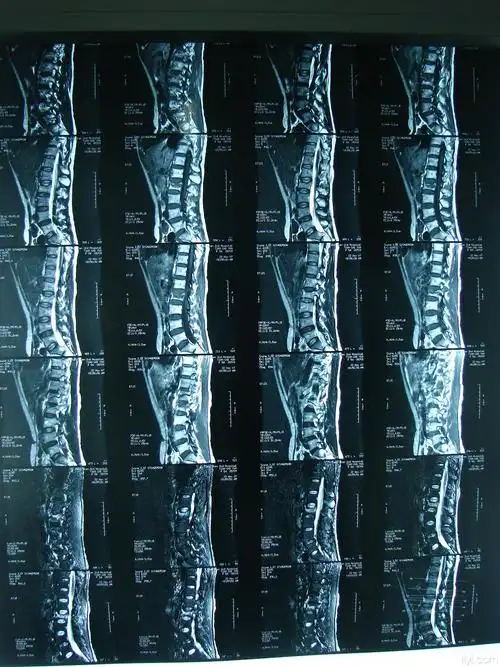

经皮椎弓根螺钉复位内固定治疗腰2椎体爆裂性骨折(ssm)

高处跌落腰椎爆裂骨折

胸腰椎爆裂性骨折并不全瘫手术治疗 - 好大夫在线

59岁男性腰椎爆裂骨折1例

患者,女,55岁 第二腰椎爆裂性骨折

腰2椎体爆裂性骨折